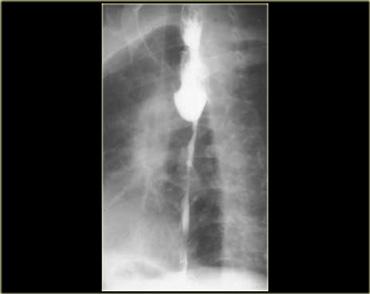

Ngoài cùng bên trái là hình ảnh bệnh nhân ung thư có hẹp thực quản.

Hẹp không đều, không đối xứng gợi ý mạnh đến ung thư.

Hẹp thuôn nhọn đều đặn, đối xứng là đặc trưng của nguyên nhân lành tính, tuy nhiên các hẹp ác tính cũng có thể có đặc điểm tương tự và bắt chước tổn thương lành tính.

Kế bên là hình ảnh bệnh nhân ung thư có hẹp thực quản giống co thắt tâm vị.

Bệnh lý ác tính đoạn thực quản xa có thể rất giống co thắt tâm vị.

Nếu nhu động thực quản bình thường, có thể loại trừ co thắt tâm vị.

Tuy nhiên, nếu bất thường, các đặc điểm hình ảnh tinh tế như: hẹp không đối xứng, không đều, đột ngột hoặc ở vị trí cao, bất thường niêm mạc, hoặc bất thường cố định sẽ gợi ý chẩn đoán.